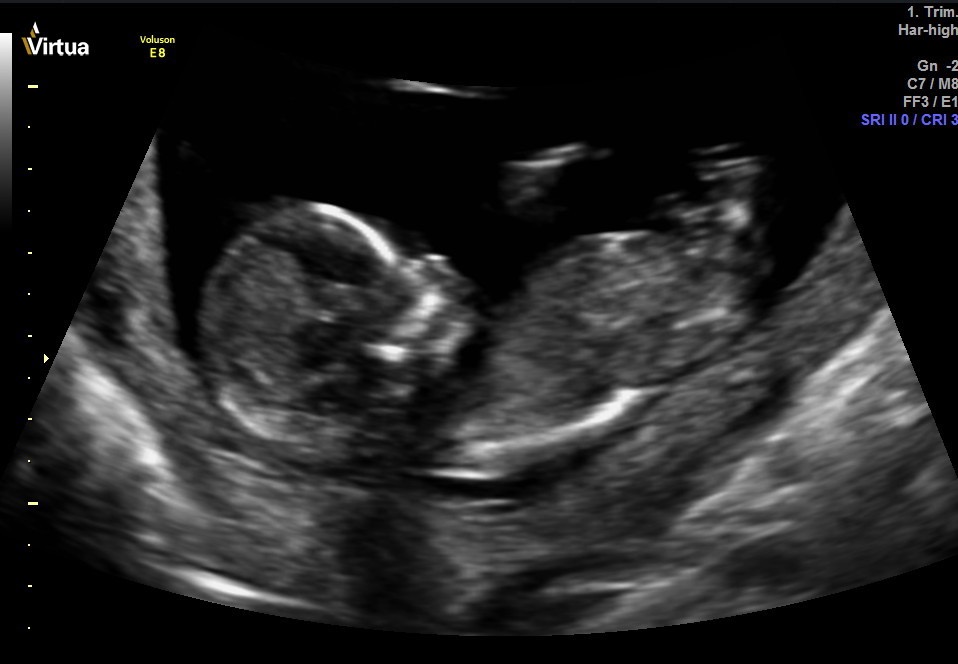

I don't see a nub, but I'm terrible at looking at these things. Can anyone guess the gender? Thank you for your help! I will come back and update on Thursday since we are going for a private scan. Hopefully baby cooperates!Attachment 34055Attachment 34056Attachment 34057Attachment 34061